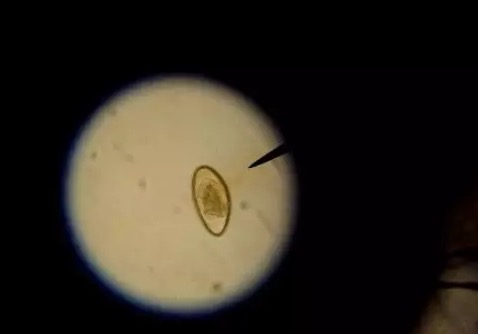

在条件允许下,最好是能先诊断是什么类型的寄生虫,再选择对应的驱虫药物,这样能提高治愈率,借助镜检技术辨别寄生虫类型是比较精准的手段。

▲显微镜下的蛲虫卵(蛲虫是线虫属下的一种寄生虫)

如果找不到镜检机构,一般肉眼能见到的虫子,基本是线虫类的。